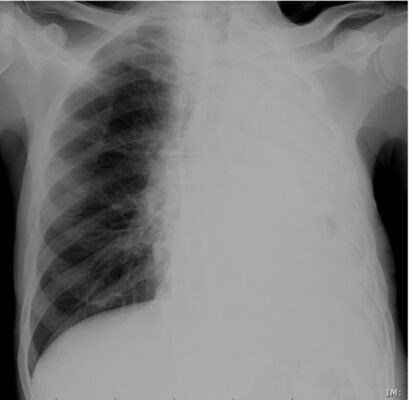

Tình huống: Anh S, 31 tuổi, đến khoa cấp cứu trong tình trạng khó thở cấp tính. Hình chụp X quang ngực thẳng của anh được thể hiện trong Hình 1.

- Như bạn có thể thấy, toàn bộ nửa phổi trái của anh S bị mờ.

- Trở lại ca bệnh (anh S) với hình chụp X-quang phổi thẳng có mờ nửa phổi trái. Bất thường ở đây là gì?

- Hình ảnh cho thấy có sự dịch chuyển của tim và khí quản về phía phổi bị mờ (Hình 9). Đây là đặc điểm của xẹp toàn bộ một phổi. Do độ tuổi (31) và tiền sử mắc bệnh hen (bạn đã hỏi về bệnh sử), rất có thể là biểu hiện xẹp phổi do một nút chất nhầy gây tắc nghẽn.

- Anh S đã được chụp CT, cho thấy tắc nghẽn ở phế quản chính bên trái và nút nhầy sau đó đã được lấy ra bằng nội soi phế quản.